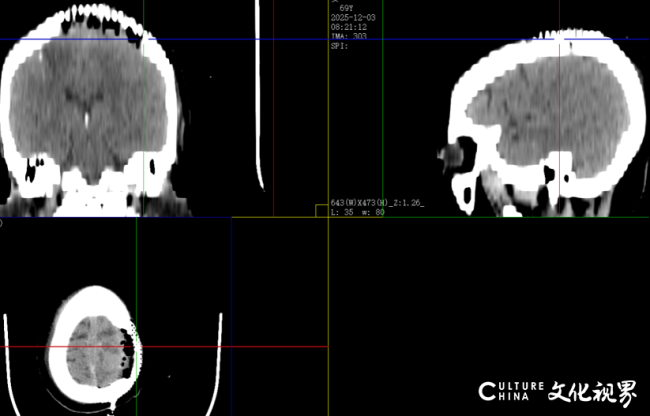

肿瘤及受侵犯颅骨

术后CT提示颅骨塑形良好,肿瘤切除范围满意,术区干净无异常出血